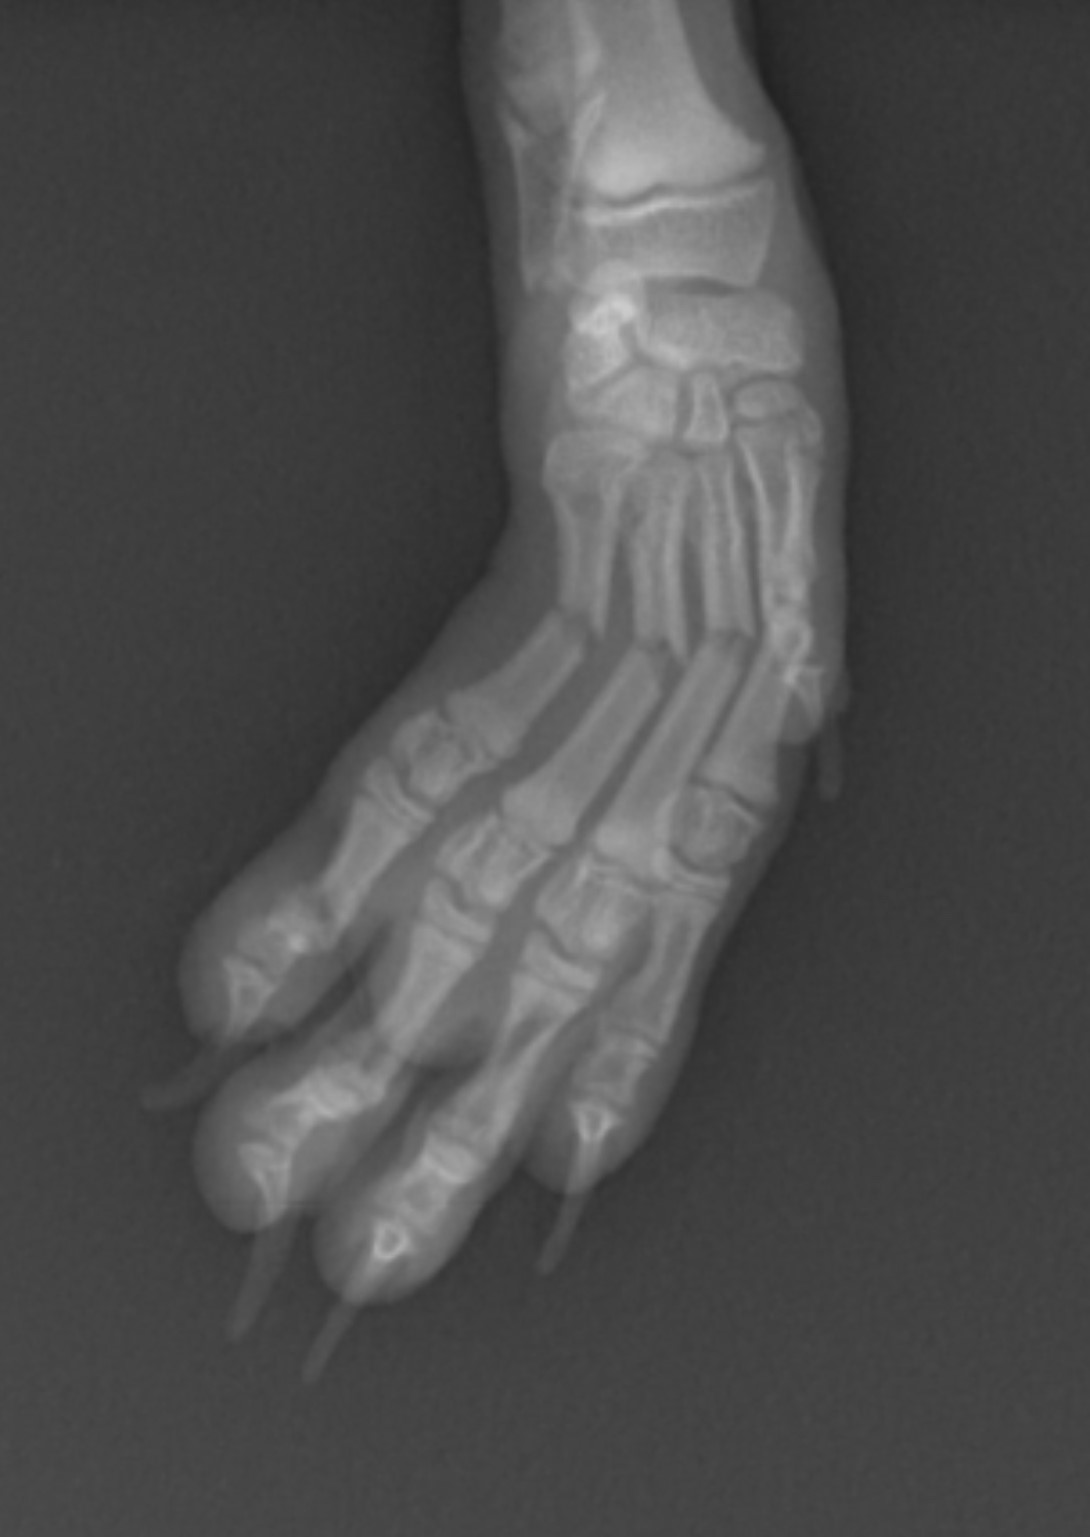

骨折2

この症例は中手骨骨折で4本折れています。1本のみの場合や場所によっては手術をせず外固定で

経過をみることもありますが、この場合は外固定で回復する見込みは低く、手術を行いました。